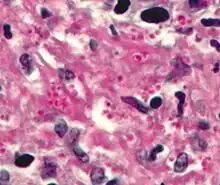

Studiet af væv kaldes histologi, mens studiet af sygt væv kaldes histopatologi. Den traditionelle metode til undersøgelse af væv er at betragte ultrafine snit af væv indstøbt i paraffin og behandlet med farvestof i et lysmikroskop. Inden for de seneste årtier er nye undersøgelsesmetoder blevet udviklet og forfinet, herunder elektronmikroskopi og histokemiske metoder, hvilket har forøget den opnåelige detaljeringsgrad. Ved hjælp af disse metoder er det blevet lettere at studere sygt væv og stille en præcis klinisk diagnose.